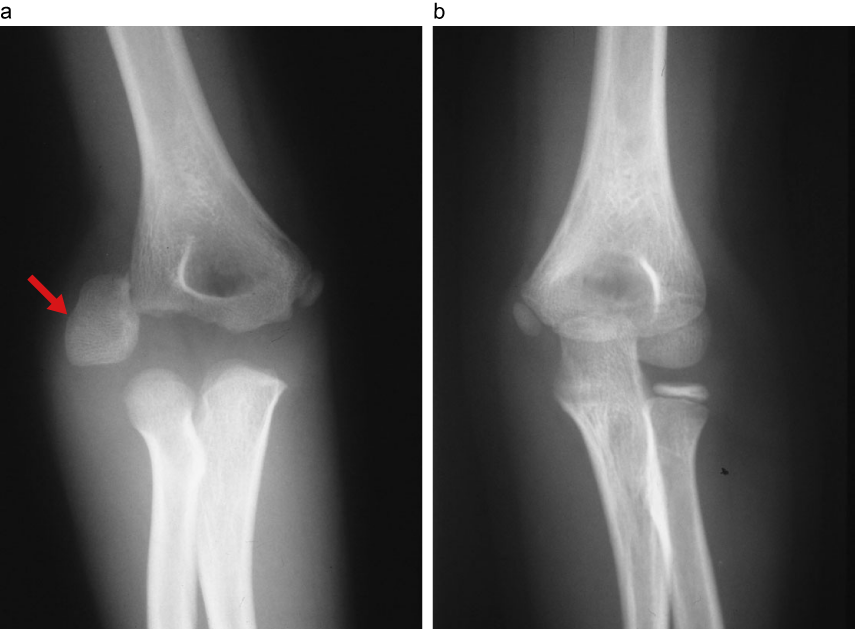

7歳男児、右上腕骨外側顆骨折

a:右上腕骨外側顆骨折。(→)上腕骨外側顆骨片が外側に90°回転している。

b:左。反対側と比較すると転位が明らか。

雲梯から転落受傷、小児は骨端核があるため骨折の診断が難しい。必ず対側のX線写真と比較する。